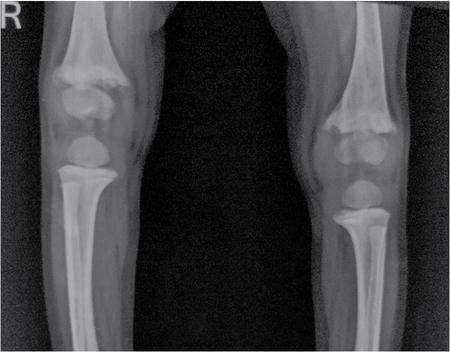

MISCELLANEOUS PAEDIATRIC RADIOGRAPHY – TECHNIQUES AND INTERPRETATION: SKELETAL SURVEY Padma V. Badhe The skeletal survey, generally performed in children, is a set of radiographs done in order to evaluate the entire skeleton. A skeletal survey, commonly used to evaluate skeletal dysplasias, acquired metabolic disorders and suspected child abuse, is still the key radiological investigation for the same. Hence, an explicit understanding of the technique along with the common disorders forms the basis of making a diagnosis in these paediatric pathologies. A skeletal survey is done for various skeletal dysplasias, non-accidental injury (battered baby syndrome) and suspected child abuse. It can also be done in cases of metabolic bone diseases, disseminated infections, multiple myeloma, eosinophilic granuloma. It is also used in evaluation of metastatic bone diseases and polyarticular arthropathy. Orthogonal views of the skull, spine, pelvis and one extremity are taken, preferable in standing position. For preterm babies/newborns, AP and lateral views of babygram may be taken. Projections: For skeletal dysplasias: Additional views: Both extremities may be taken if epiphyseal abnormalities and limb asymmetry is present. Focused views for specific pathologies may be taken. When a diagnosis remains uncertain, 1 year follow up is usually recommended. For preterm babies/newborns: AP and lateral views of babygram may be taken with additional specific views for extremities. For suspected non-accidental injury (NAI): AP and oblique view of chest is taken for better evaluation of the ribs. AP view of abdomen with pelvis. Both upper and lower limbs are evaluated. In lower limbs, two projections in AP and lateral (one with both femur including hip and knee joints; and another for foot and ankle) is taken. AP and lateral views of whole spine, skull. Oblique view of hands. A babygram should be avoided in cases of NAI, as subtle fractures are easily missed. Proper legal documentation while taking the views is very important and ideally two health care professionals must be present. For metabolic disorders: entire skeletal survey is usually not required. Specific views of hands, knees and spine may be taken with additional views depending on the suspected pathology. Centring point: Varies according to the part being examined. Angulation, collimation and orientation: Varies according to the part being examined. Images must be well collimated to obtain lower radiation dose. Detector size: Varies according to the part being examined: 8″ × 10″, 10″ × 12″, 11″ × 14″. Exposure: Ideally high kVp images are taken to reduce radiation dose. But in suspected NAI, low kVp/high mA images are recommended to better demonstrate findings. SID (Source Image Distance):100 cm Grid: Grids are not routinely used to image spine, pelvis, skull and abdomen in children. Radiation dosage: 0.3–3 mSv Essential image characteristics: Adequate spatial resolution, high signal to noise ratio, low kVp (50–70) for high contrast should be done. Excellent bone and soft tissue details are required. The presentation of skeletal dysplasia can range anywhere from minimal stunting of growth and bowing of limbs to severe dwarfism and multiple fractures. Knowledge of the commonly encountered dysplasias with an approach to arrive at a diagnosis is vital in any Radiologist’s practice The following flow chart summarizes the classification of important skeletal dysplasia: The following table summarizes the various dysplasias affecting the axial skeleton: TABLE 7.5.1.1 The following flow chart summarizes the working approach to skeletal dysplasias: Osteopetrosis (Albers-Schonberg disease/Marble bone disease) (Fig 7.5.1.1): Osteopetrosis clinically presents with anaemia/thrombocytopenia or cranial nerve compression. Radiological features include generalized increase in bone density with loss of medullary space. However, cortico-medullary appreciation with cortical thinning is also rarely seen. Bone within bone appearance with Erlenmeyer flask deformity is also noted. Pyknodysostosis (Figs. 7.5.1.2 and 7.5.1.3): patient presents with short stature. Unlike osteopetrosis, there is no anaemia. Radiographs show generalized increase in bone density with preserved medullary canal. There is mandibular hypoplasia with obtuse angle. Acro-osteolysis is also a feature. Dental caries with osteomyelitis of the jaw may be seen. Sclerosing dysplasia presenting as wavy undulating new bone formation. Usually monomelic, lower limb and along one side. The classic appearance is described as Dripping candle Wax sign. It is a Sclerosing dysplasia with radiological features of symmetric juxta-articular involvement in epimetaphyseal region. They are 1–10 mm in diameter and uniform in size. No metabolic activity is seen on bone scans. This skeletal dysplasia shows diffuse decrease in bone density with paper-thin cortex. Fractures heal in normal time but shows callus with poorly cellular matrix. Wormian bones and enlarged sinuses may be seen. Codfish vertebra (Biconcave vertebra) may be seen. Metaphyseal corner fractures are not seen in osteogenesis imperfecta that helps to differentiate it from battered baby syndrome. There are four types of OI out of which type one is most common (Figs. 7.5.1.6 and 7.5.1.7). The radiological features of MPS include Osteopenia and Universal platyspondyly. The intervertebral disc spaces are maintained. Proximal pointed metacarpals is an important radiological finding. Hurler’s syndrome show anteroinferior beaking with short and wide metacarpals. Varus deformity of humerus is characteristically seen in Hurler’s syndrome (Fig. 7.5.1.8). Mental retardation & corneal clouding is seen in Hurler’s syndrome whereas these Hunter’s disease has normal intelligence with no corneal clouding. Morquio’s syndrome shows central beaking (Fig 7.5.1.9). This skeletal dysplasia shows normal bone density with rhizomelic limb shortening and normal trunk. Narrowing of spinal canal is classically seen with decrease in the Interpedicular distance caudally. Other radiological features include trident hand (separation of middle & third fingers), Champagne glass pelvis (short, flat ilia and small sciatic notch), bullet nose vertebra and overexpansion of skull with narrow foramen magnum (Fig. 7.5.1.10). This skeletal dysplasia is characterized by normal bone density with dwarfism and normal craniofacial skeleton. The interpedicular distance is normal. There is severe platyspondyly with anterior tonguing (disappears at older age). Other radiological features include increased disc space, short stubby metacarpals, small irregular epiphysis and widened metaphysis. Anterior tonguing is a feature of Pseudoachondroplasia. This form of skeletal dysplasia involves the spine and epiphyses (Fig. 7.5.1.11). There is normal bone density with rhizomelia. Spine and Pelvis can be involved. Premature osteoarthritis can be seen. The other characteristic features include Platyspondyly and small irregular epiphysis. There are two forms Spondyloepiphyseal dysplasia Congenital and Spondyloepiphyseal dysplasia Tarda. Spondyloepiphyseal dysplasia Congenita is Autosomal dominant and shows pear-shaped vertebrae. Spondyloepiphyseal dysplasia Tarda is X Linked recessive with heaped up vertebrae. It has two forms. The first form is Conradi Hunermann syndrome which is autosomal dominant characterized by asymmetric limb shortening with metaphyseal flaring (Fig. 7.5.1.12). The Autosomal recessive form is Fatal in first few years. Rickets: Rickets refers to deficient mineralization of the growth plate in the paediatric population due to deficiency of vitamin D. In an immature skeleton, there is abnormal mineralization at the zone of provisional calcification in the metaphysis due to osteoid deposition resulting in widening of the growth plate. The features of rickets include fraying, splaying and cupping (Fig. 7.5.1.13). Fraying denotes indistinct margins of the metaphysis whereas splaying denotes widening of metaphyseal ends. Term ‘Cupping’ is used for increased concavity of the metaphysis. These findings are typically seen involving areas of active growth (e.g. distal femur and proximal tibia in the knee) Bowing is a result of associated osteomalacia leading to weakening of weight-bearing lower limb bones. Other bone deformities such as genu valga, genu varum, protrusio acetabuli can also be seen. The lower ribs may also be drawn inwards inferiorly by the attachment of the diaphragm this is called Harrison’s sulcus. Scurvy: Scurvy is a result of dietary deficiency of Vitamin C (ascorbic acid). The classic presentation is that of a patient with an increased bleeding tendency and osteopenia with poor wound healing. Features of scurvy include generalized osteopenia with cortical thinning termed as ‘pencil-point’ cortex. Other radiological findings include the periosteal reaction due to subperiosteal haemorrhage. Expansion of the costochondral junctions occurs forming scorbutic rosary. Bleeding into the joint spaces may result in hemarthrosis. Circular, opaque radiologic shadow surrounding epiphyseal centres of ossification may result from bleeding (Wimberger ring sign) (Fig. 7.5.1.14). Frankel line may be seen. It represents dense zone of provisional calcification. Lucent metaphyseal band is seen underlying Frankel line called as Trümmerfeld zone. Metaphyseal spurs may be seen that result in cupping of the metaphysis (Pelkin spur). Pelkin fracture (metaphyseal corner fracture) can also be seen. Images obtained must be of good resolution with adequate bone and soft tissue details. Additional views: They have already been described in positioning. CT Brain in can be done in cases of NAI to look for subdural hematomas. A skeletal survey is the first-line imaging modality for evaluation of skeletal dysplasia, nonaccidental injury and metabolic bone diseases. The skeletal survey must be tailored according to the respective indication. It helps to characterize syndromic patterns in skeletal dysplasias, with evaluation of complications. In cases of diagnostic dilemmas, additional focused view and occasionally yearly follow-up is recommended. A high index of suspicion is needed in utilizing skeletal survey as a diagnostic modality in NAI. At the same time, one must also remember the legal and social implications of making this diagnosis. BABYGRAM Babygram is a colloquial term used for a radiograph of the whole body of a newborn or just the chest and abdomen (thoracoabdominal babygram) on a single image. As the name suggests it is a rather non-targeted study. It is most commonly requested after line placement. Evaluation of skeletal abnormalities in a deceased foetus is typically performed using anteroposterior and lateral views of a babygram. It helps in pointing out skeletal causes of death in stillborn or dead foetuses. This will help the treating physician and parents understand the reason for baby’s death. This will also help in future genetic counselling of the couple. Sometimes chest or abdominal radiographs of the baby are requested but due to radiographers error or inexperience with small babies, there is inclusion of the region not to be assessed leading to a false babygram. Babygram is most frequently done after line placement in neonates, to view the position of the umbilical vein or artery catheter and to confirm appropriate placement. It is a useful modality in skeletal dysplasias (Fig. 7.5.1.15) like osteogenesis imperfecta, thanatophoric dysplasia and chondrodysplasia punctata. It can also be used for skeletal deformations probably caused by foetus akinesia and in cases of Caudal regression syndrome. In stillborn foetuses, it is used for evaluation of skeletal dysplasias prior to an autopsy (Fig. 7.5.1.16). It is also used in screening for surfactant deficiency and in cases of Necrotizing Enterocolitis in preterm babies where it can help to see the bowel dilatation, intramural and portal venous gas. It can be done in aneuploidies like trisomy 18 and in cases of sudden infantile death syndrome. All the essential equipment and room need to be prepared including the exposure factor. This should be done prior to placing the baby on the table to prevent any neonatal heat loss. Ensure that the baby is correctly identified. Give brief explanation to the patient’s parents regarding the procedure, its risks and benefits. Ensure that the accompanying relative is not pregnant (if female). Parents/guardians/nurses should be instructed to hold the baby with arms above the head and legs straight down. Sandbags/tapes can be used to immobilize the baby. Avoid taking the radiograph when baby is crying. Normal appearance: The endotracheal tube should lie in the lower third of trachea, distance can vary with position of baby’s head. Umbilical artery catheter has an inferior dip along the internal iliac artery, which then turns superiorly along the aorta. The tip should lie in the mid-thoracic aorta (T6–T10) or lower (L3–L4) away from aortic branches to prevent any thrombosis. Umbilical venous catheter does not have the inferior curvature, but rather a posterolateral angulation to the right near the liver through the ductus venosus. The tip should lie in the superior IVC or right atrium at T8/T9 vertebral level (Fig. 7.5.1.17). Portal venous gas may be seen initially after insertion. In a stillborn foetus, the approximate gestation age of the foetus and corresponding ossification centres must be known. In early gestation, the lack of appearance of an ossification centre may be mistaken for skeletal dysplasia. Both chest and abdomen should be included. In a rotated patient, the distance between the spinous process to medial end of clavicles will be asymmetric. The medial end of clavicle should overlap the lung apex, if above, suggests lordotic image. Motion artefacts to be reduced as much as possible. A crying neonate may result in an expiratory film, and hence must be evaluated accordingly. In evaluation of skeletal dysplasias in the newborn, additional views of skull and hand have to be obtained. Baby gram is a useful diagnostic investigation for position of the paediatric umbilical catheters. It helps in general survey in skeletal dysplasia (Fig. 7.5.1.18). It is a simple, effective study in deceased foetus for diagnosis and further counselling, sometimes obviating the need for an autopsy. As baby gram is a non-targeted study, it increases the dose of radiation for the baby. As the exposure settings remain same for the entire body of the baby, the quality of the image decreases. This increases the chances of missing subtle findings. The babygram in a neonate is currently used to localize umbilical catheters. In stillborn fetuses, it is still an important study for documenting and confirming skeletal dysplasias. Understanding the normal appearance as per gestation age and patterns of various common skeletal dysplasias is essential for evaluation. Being a non-targeted study, it should not be used as an alternative study to evaluate the chest or abdomen considering radiation exposure and poorer image quality. INVERTOGRAM Invertogram was first described by Wangensteen and Rice in 1930. It was used as a first investigation to be ordered in evaluation of infants with clinically diagnosed or suspected Anorectal Malformation (ARM). ARM is a serious but surgically treatable congenital malformation with approximate incidence of 1 in 5000 live births. Though the diagnosis of this condition is based on clinical history and physical examination, imaging plays an important role in deciding the type of ARM, and associated complications to aid in management. International classification of anorectal malformations is as follows. Syndromic association is seen as a part of VACTERL defects, trisomy 21 13 and 18, Klippel Feil syndrome, cat eye syndrome etc. The main indication of Invertogram is to evaluate anorectal malformation in a neonate. A radio-opaque marker is placed over the external anal opening. Infant is held inverted by holding both thighs, maintaining this posture for at least 5 minutes before taking an X-ray in true lateral position (Fig. 7.5.1.19). Exposure is made during inspiration. The Invertogram should ideally be done 24 hours after birth as, the rectal gas may not reach the terminal segment if study is done too early. Pubo-coccygeal line (PCL) is drawn from upper border of pubic symphysis (which corresponds to centre of pubic bone on lateral X-ray) to sacrococcygeal junction. I point is the inferior most point of ischial ossification centre. A line which is drawn parallel to PC line passing through the I point is called I line. ‘A’ point is represented by marker placed at anal pit. The position of rectal pouch gas shadow is observed with respect to these lines and appropriate diagnosis is made (Fig. 7.5.1.21). A diagnosis of high ARM is made when gas shadow of rectal pouch is cranial to PCL. If rectal pouch gas shadow is in between PCL and I line, it is called as intermediate ARM and if it is caudal to I line, it is diagnosed as low ARM. Gas in urinary bladder or vagina or beaking of gas shadow of rectal pouch indicates fistula into one of these sites. Associated congenital abnormalities like spinal defects are also looked for in the invertogram (Fig. 7.5.1.22). Invertogram done too early (less than 24 hours) may not demonstrate rectal gas. Meconium plugging the terminal segment gives false position of the rectal gas. Positioning can cause discomfort to child and an irritated crying child actively contracts the sphincter muscles, pushing the gas shadow higher. Rectum may be pulled cephalad due to gravity in inverted position. The rectal gas may escape through an associated fistula. Erroneous interpretation can also occur due to sacral anomalies and when gas in vaginal cavity is misinterpreted as distal rectal gas. Both ischial bones should superimpose and terminal blind loop should be well distended. It is an easily available modality and can be done quickly, does not require additional equipment. It has lesser radiation dose as compared to CT invertogram. It provides a rough guide as to the type of ARM and decides management. Higher localization of obstruction due to various causes like meconium plugging, imaging done too early etc. as described above in pitfalls. It is more uncomfortable to the baby as compared to the prone cross-table lateral view, and a crying baby contracts the puborectalis leading to erroneous results. K. L. Narasimharao et al. modified the technique and proposed cross-table lateral view for evaluation of infants with ARM’s which has shown equal or better information and has now replaced invertogram (Fig. 7.5.1.23). Prone cross-table lateral view is considered equivalent or even better in determining the level of anomaly. Positioning is in this view is prone in genupectoral position (at least for 3 minutes). It is taken in true lateral and during inspiration. The lines used to delineate types of ARM is essentially the same as in an invertogram. It is preferred over invertogram as relatively easy positioning of the infant and less discomfort allows for better cooperation of neonate during the study. It also eliminates the effect of gravity. ARM with fistula is better delineated as, in an invertogram, fistula/gas is at the highest level and gas may escape through it. CT invertogram is another modality that delineates anatomy better but is rarely used. In the era of cross-section imaging, MRI and USG have opened new modalities for accurate diagnosis of ARM, but invertogram being readily available, inexpensive, quick and cost-effective is used as first investigation for evaluating a patient with suspected or confirmed case of ARM. Cross-table lateral view has replaced invertograms as it is more patient-friendly and equally effective. UPPER GASTROINTESTINAL SERIES Rushit S. Shah An upper gastrointestinal (GI) study is a radiographic examination of the GI tract from the pharynx to the ligament of Treitz after oral administration of contrast agent. The use of upper GI studies is gradually declining with the increasing availability of paediatric endoscopy and the challenge for the modern radiologist to work in conjunction with the surgeon and gastroenterologist to select the right patients for an upper GI series. However, the upper GI series remains the key for demonstrating many anatomical abnormalities. The upper GI series is also useful in evaluating gastro-oesophageal reflux in conjunction with 24 pH monitoring. The upper GI examination is useful in evaluating many conditions including but not limited to: